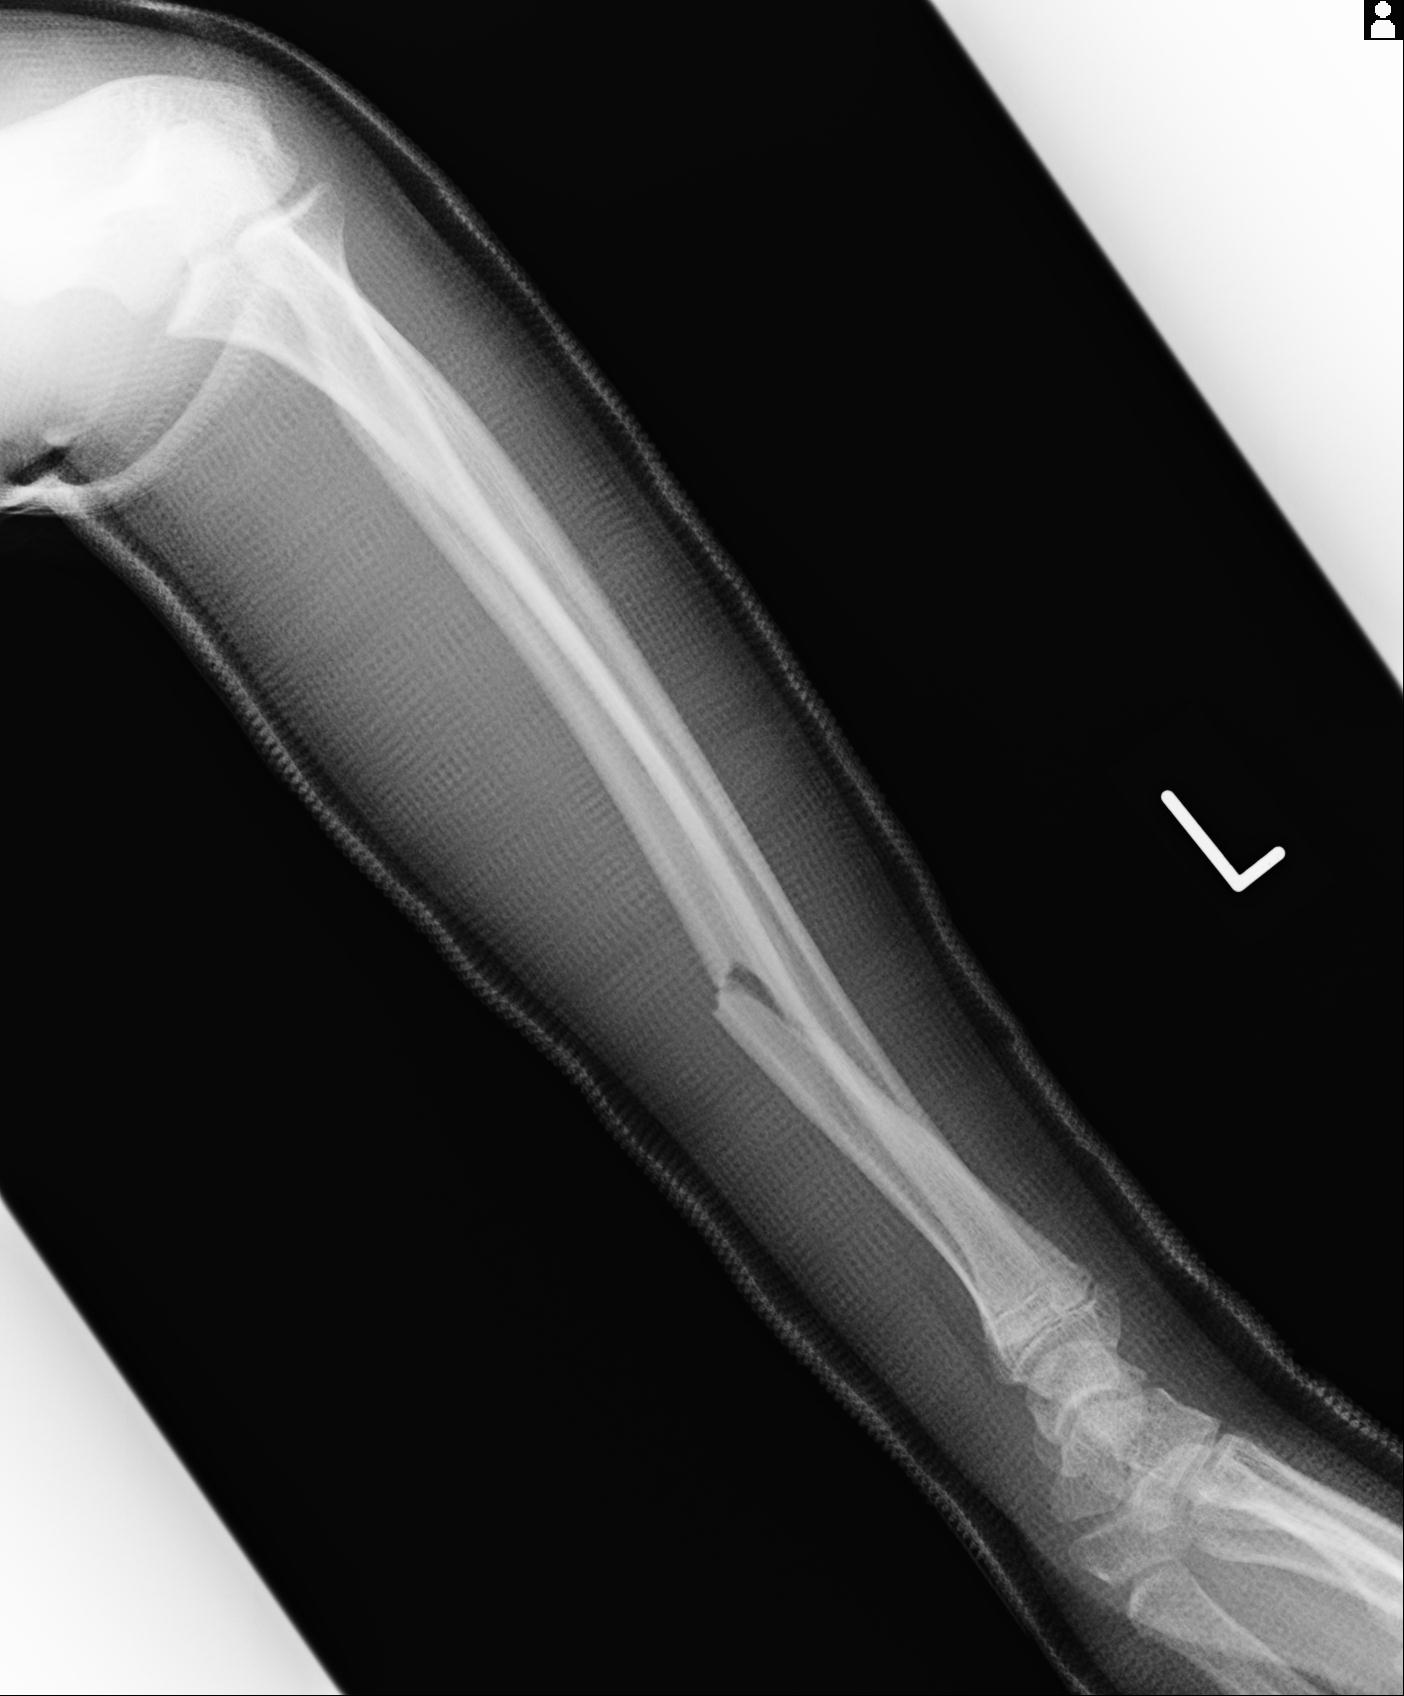

110211 1/6 1/8 左前腕 4R 15歳男性 橈骨骨幹部骨折